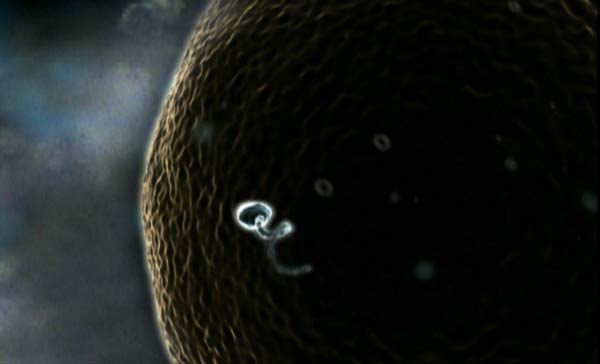

La foto muestra el viaje del espermatozoide hasta el óvulo. Es el momento en el que se va a producir la fecundación.